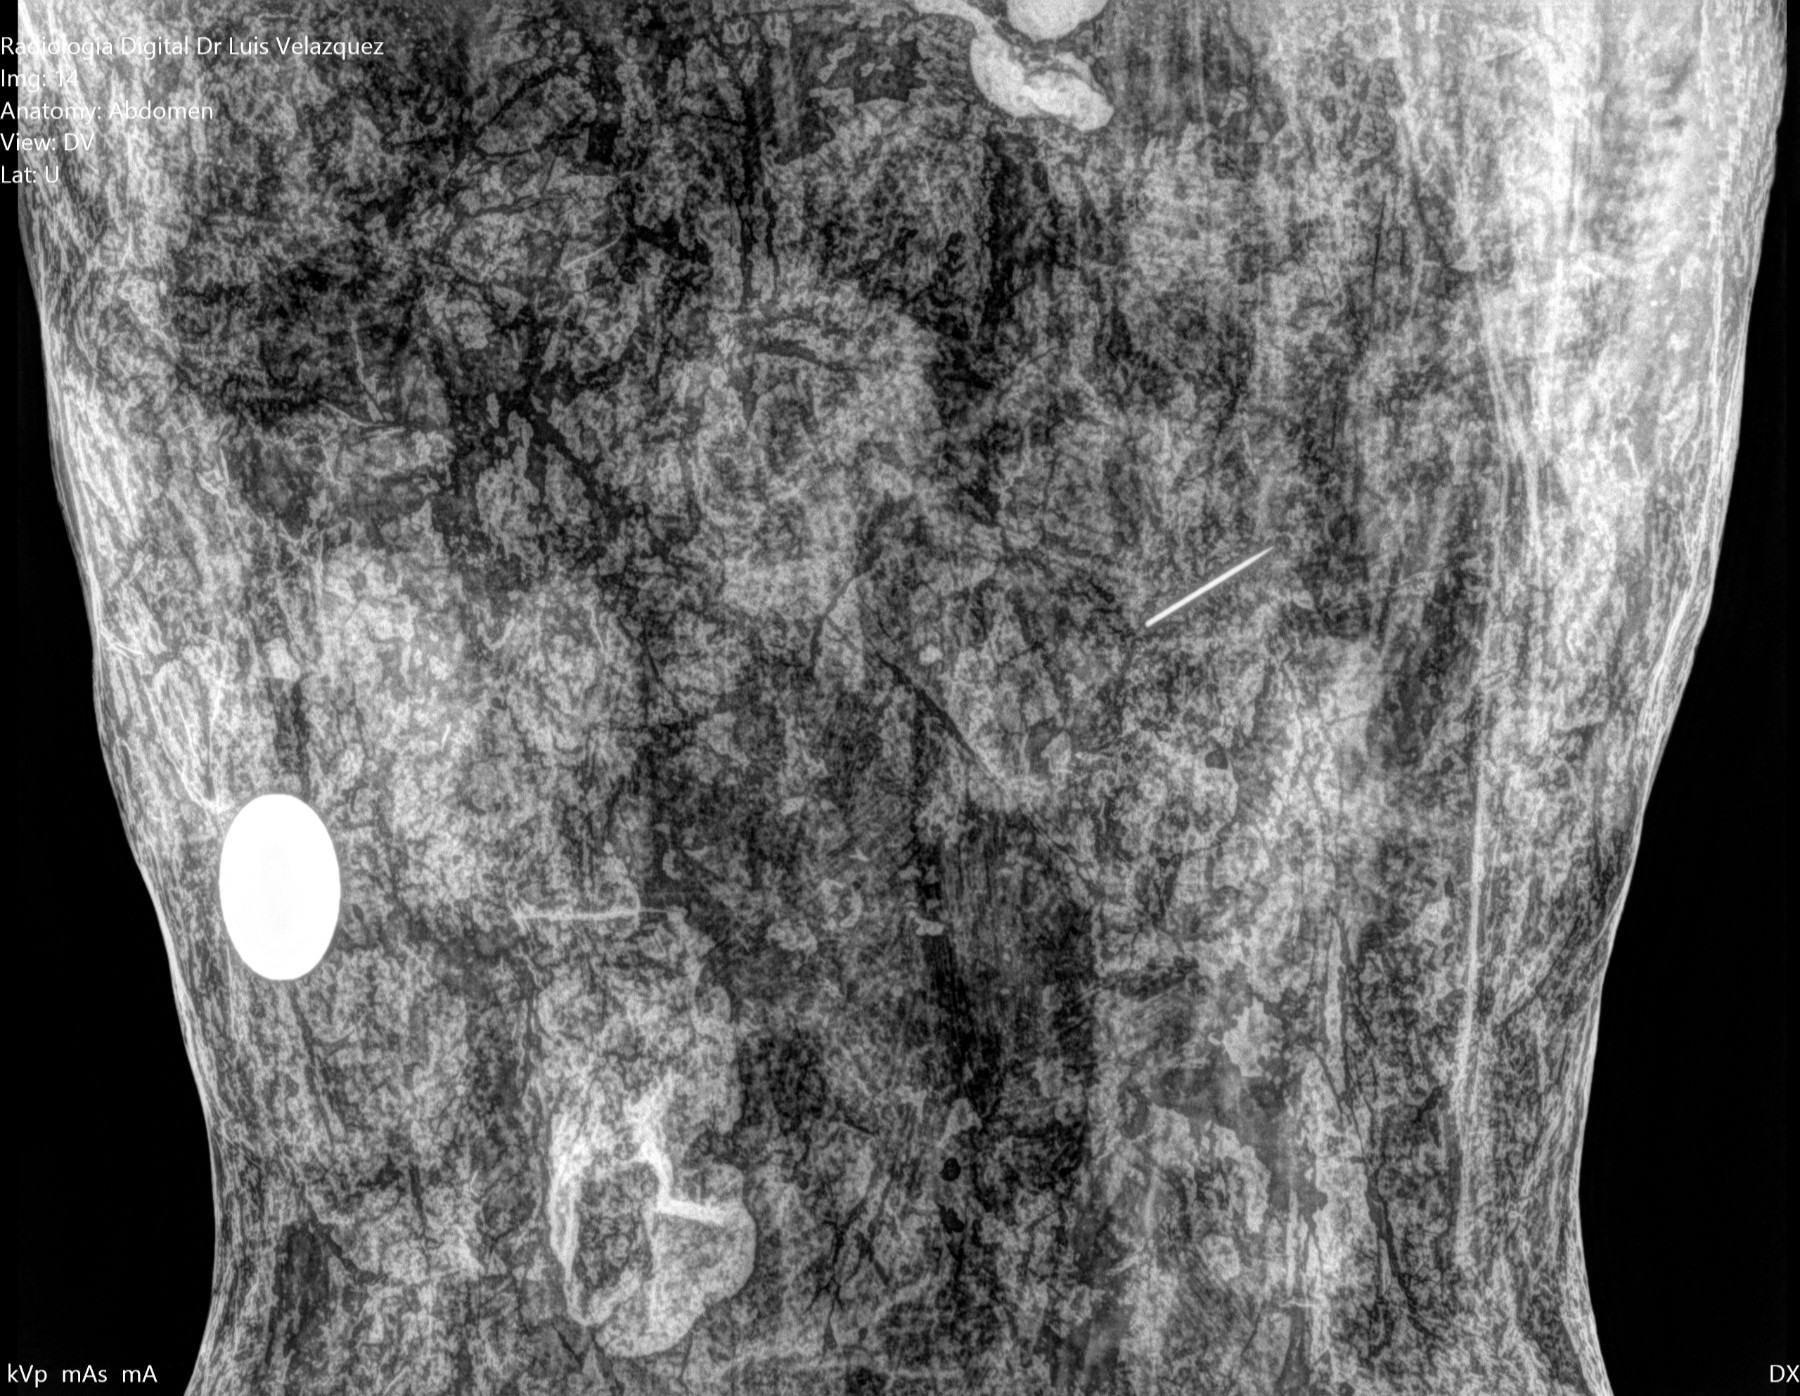

Cambios Térmicos en las Extremidades de Caballos,

Asociados a Golpes y su Evaluación por Termografía.

Los caballos de salto, en competencia, pueden derribar obstáculos y lastimarse. Si se golpean, no siempre claudican. Considerando al calor como un signo de inflamación, se evaluaron los cambios térmicos de 6 áreas de las extremidades torácicas y pelvianas de 23 caballos de salto en nivel de competencia de 1.05 a 1.60 m de altura, por medio de termografía durante 4 días de competencia (N=2208 áreas).